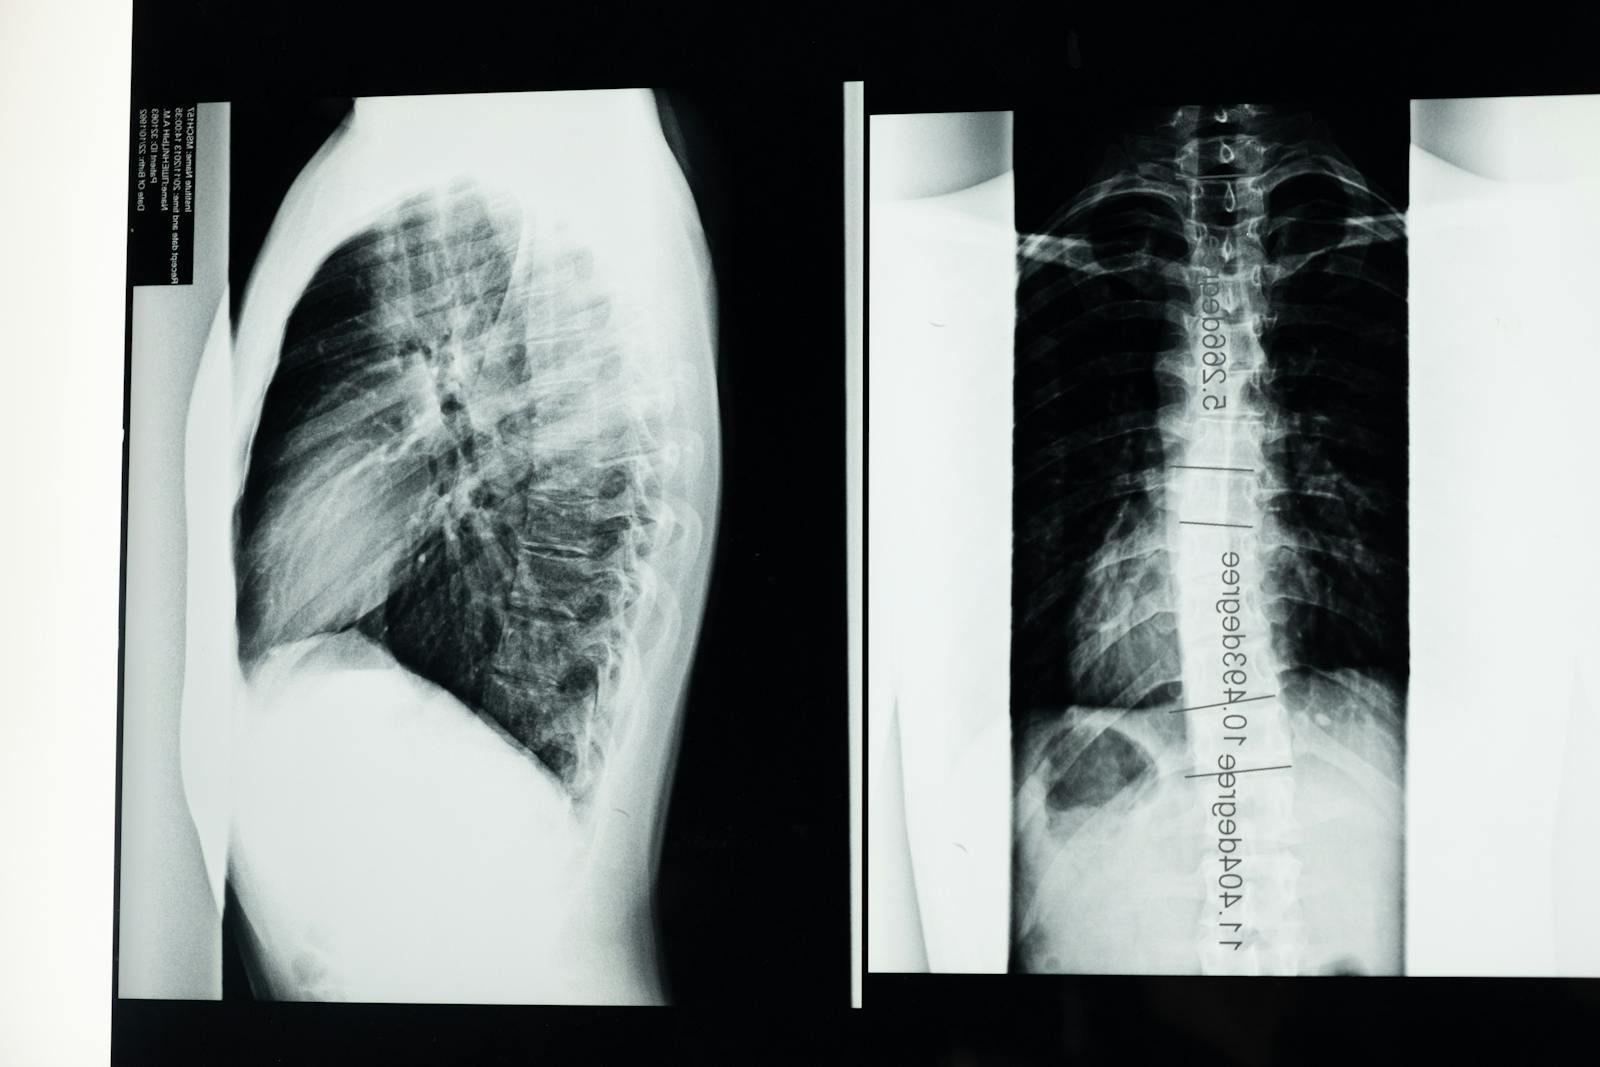

A landmark systematic review published in medical literature found that spontaneous regression rates vary significantly by herniation type. Disc sequestration (the most severe form, where disc material completely breaks free) shows a spontaneous regression rate of 96 percent.

Disc extrusion regresses in 70 percent of cases, disc protrusion in 41 percent, and simple disc bulging in 13 percent. Furthermore, complete resolution of disc herniation occurred in 43 percent of sequestrated discs and 15 percent of extruded discs.

A separate meta-analysis reviewing eleven cohort studies found that the overall incidence of spontaneous resorption after lumbar disc herniation was 66.66 percent. Additionally, a clinical study tracking nine patients found that spontaneous resorption occurred in all patients within an average of 8.7 months following conservative management. These numbers consistently support conservative treatment as the appropriate first-line approach for most disc herniations.